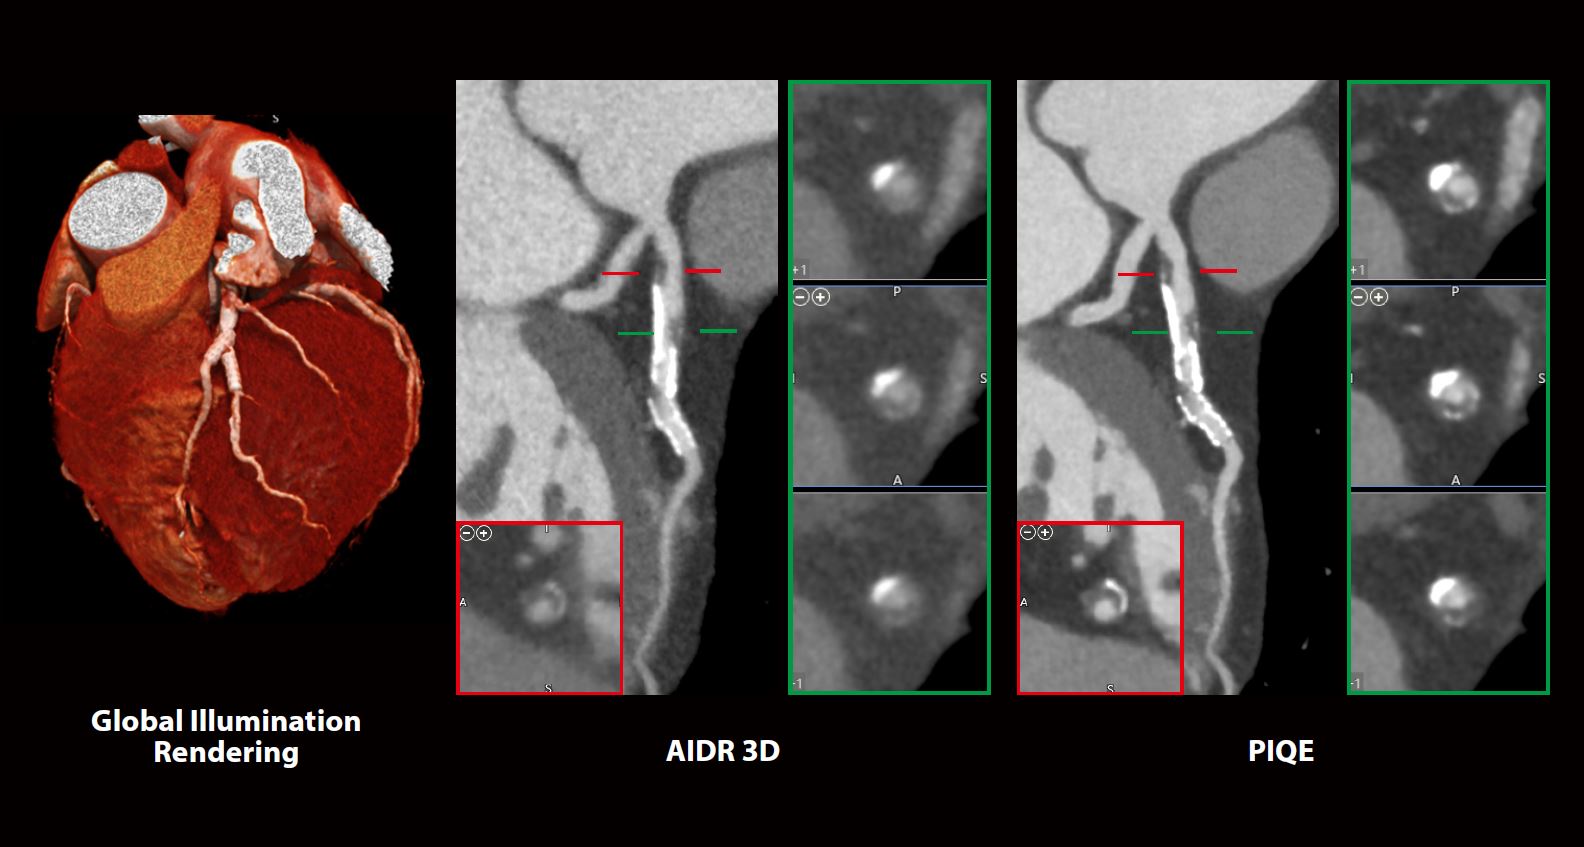

Покращена візуалізація бляшок у коронарних артеріях за допомогою Precise IQ Engine

Що мене найбільше вразило в PIQE, так це якість зображення. Він має неймовірну деталізацію. Завдяки реконструкції PIQE кількість артефактів від кальцинованих бляшок мінімізується.”

У цього 56-річного чоловіка з ІМТ 26,2 кг/м2 та попереднім встановленням коронарного стента спостерігався нетиповий біль у грудях. Його направили на КТ дослідження коронарних судин. Зображення були реконструйовані за допомогою Precise IQ Engine (PIQE) Deep Learning Reconstruction (Штучна нейронна мережа глибокого навчання).

Результати

Стенти присутні в лівій передній низхідній (LAD) і другій діагональній гілці. У лівій головній частині LAD, проксимальніше стентів, спостерігається значна кальцифікована бляшка. PIQE забезпечує чіткішу деталізацію з точно визначеним кальцифікованим і некальцифікованим вмістом і меншим висвітленням від кальцію та стентів порівняно з адаптивним ітеративним зменшенням дози (AIDR) 3D.

Переваги PIQE

- Більш чіткі анатомічні деталі

- Знижені артефакти від кальцію

- Без додаткової дози

Висновок

PIQE забезпечує підвищену просторову роздільну здатність для чіткої візуалізації

просвіту судини для кращої оцінки повторного стенозу стента. Властивості високого

контрасту до шуму обстежень PIQE також забезпечують кращу оцінку сильно

кальцифікованих коронарних артерій без втрати низькоконтрастної чутливості*2 або

збільшення дози опромінення. У цьому клінічному прикладі PIQE дозволив впевнено

оцінити просвіт судини на наявності кальцифікованих і некальцинованих бляшок і

стентів.